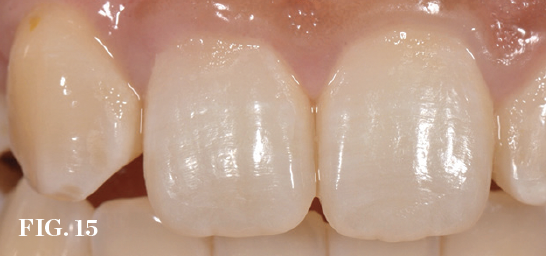

(15.) Preoperative view of a central incisor undergoing resorption (tooth No. 8). Incisionless or minimally invasive procedures can potentially enhance thesoft-tissue anatomy.

Figure 15